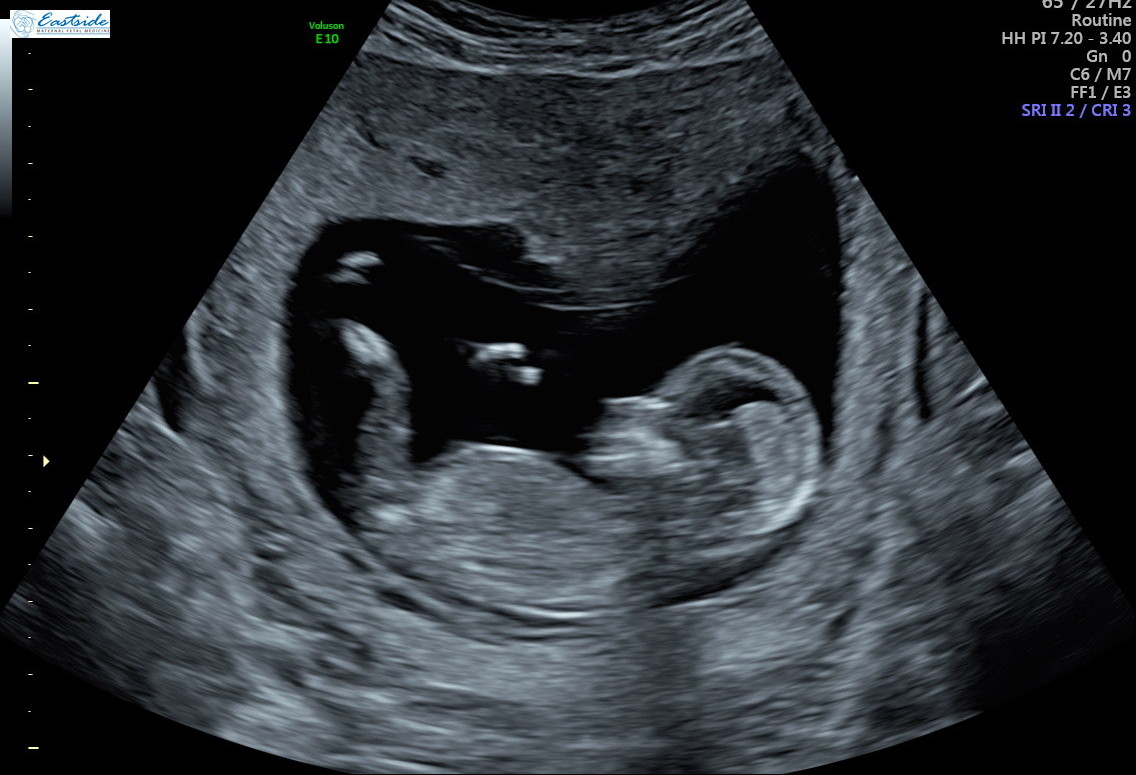

I am wondering if any experts or experienced could review the pics from my 13 week ultrasound? The tech said she was 80% sure of gender, but is it obvious to any of you? We have 3 girls so as you might guess, we are a bit anxious to find out!

Thanks! Attachment 38878Attachment 38879Attachment 38880Attachment 38881Attachment 38882Attachment 38883